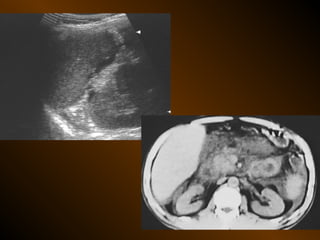

• SIÊU ÂM

– Phản âm trống, chuyển dịch

– Lượng ít

– Bản chất dịch

• X QUANG CẮT LỚP ĐIỆN TOÁN

– Mật độ

– Vị trí

– Nguyên nhân

– Phản âm, chất chứa, vỏ bọc ?

– Mật độ, bắt cản quang ?